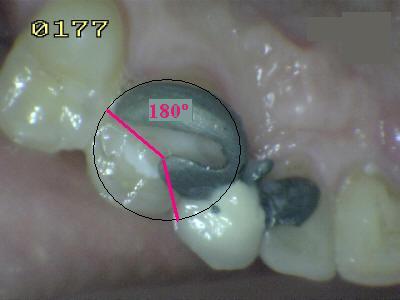

Puente Maryland

"Guía clínica para el diseño de puentes adhesivos"

Indicaciones y Contraindicaciones del Puente Maryland

* Tallado de pilares para puente Maryland